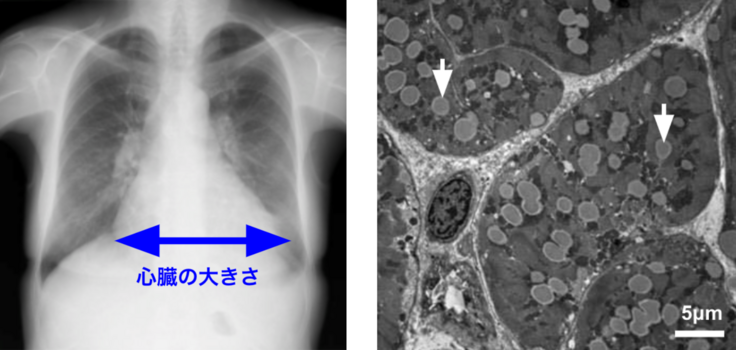

中性脂肪蓄積心筋血管症(Triglyceride deposit cardiomyovasculopathy:TGCV)は、2008年にわが国で見出された新しい疾患概念で、心臓の筋肉や血管に中性脂肪(TG)が蓄積する結果、重症心不全、心筋症、狭心症などを来す難病です。

TGCVでは、心臓の細胞内の脂質代謝に異常をきたしてTGが上手くエネルギーとして利用できずに蓄積します。

TGCVは例えていうと、心臓が脂肪細胞を心臓の筋肉や血管に蓄積してしまう、“心臓の肥満症”といえます。